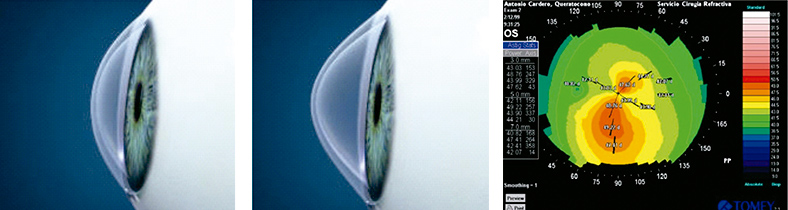

QUERATOCONO

Es una enfermedad crónica, progresiva, asintomática en donde la forma normal de la cornea se distorsiona, desarrollando una deformación en forma de cono, que modifica y altera progresivamente la visión haciendola cada vez mas borrosa.

La realización de estudios convencionales como la topografía y la paquimetría en forma periódica nos permite la estadificación y el seguimiento estricto de estos pacientes.

¿Qué son los anillos intraestromales?

Es un tratamiento ortésico compuesto de dos segmentos semicirculares de espesor y diámetro variable, de material acrílico (Perspex CQ). Es perfectamente tolerado por el organismo sin ningún riesgo de rechazo.

Es el más moderno y seguro tratamiento para tratar el queratocono.